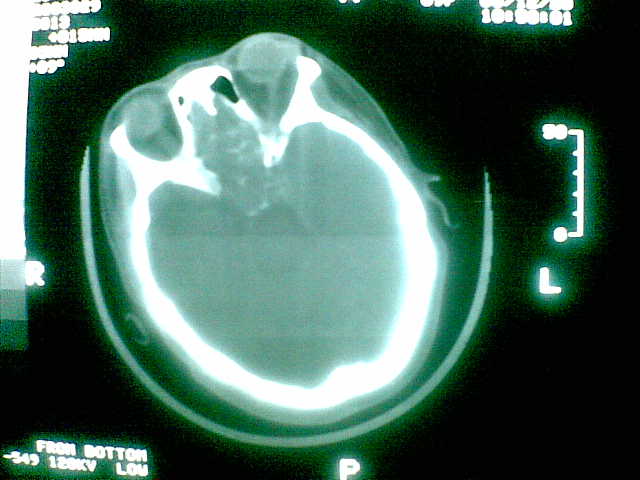

69岁 女 主因头痛就诊。大家看看起源于哪里啊

考虑起源于斜坡的脊索瘤。血管瘤待排。

考虑起源于斜坡的脊索瘤